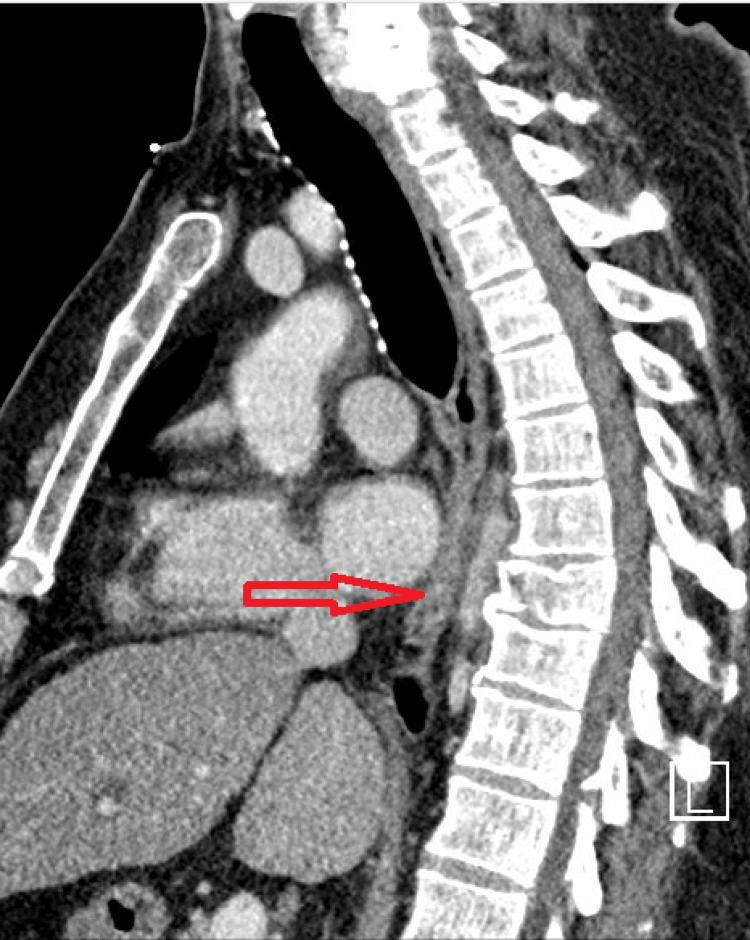

Vertebral (spinal) osteomyelitis is a rare spinal infection of the vertebral column that can be caused by bacteria or fungi. Though the initial treatment for all patients with vertebral osteomyelitis consists of antibiotics, surgery can be indicated in certain cases, such as in the presence of spinal instability or when antibiotics are not successfully eliminating the infection. Achieving spinal stability can be an important component of treating fracture-related infections, as instability can cause local damage and disrupt the healing process. The authors present the case of a patient with vertebral osteomyelitis that was not resolving with the administration of antibiotics in the context of a spinal fracture. A minimally invasive surgery was performed to achieve spinal stability and the infection soon resolved with antibiotics.

脊椎骨髓炎是一种罕见的脊柱感染疾病,可由细菌或真菌引起。虽然所有脊椎骨髓炎患者的初始治疗都包括使用抗生素,但在某些情况下,如存在脊柱不稳定或抗生素未能成功消除感染时,可能需要进行手术。实现脊柱稳定是治疗骨折相关感染的重要组成部分,因为不稳定会导致局部损伤并干扰愈合过程。作者介绍了一例脊椎骨髓炎患者的病例,该患者在脊柱骨折的情况下使用抗生素治疗后病情未得到缓解。通过微创手术实现了脊柱稳定,随后感染在使用抗生素后很快得到解决。